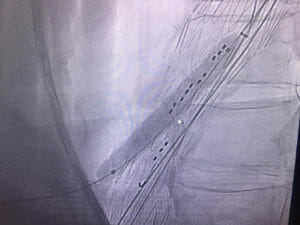

Gore Viabahn VBX balloon expandable covered stent might provide an excellent option for branched thoracoabdominal stent graft. Two VBX used today for successful bridging of coeliac axis and SMA branches. Easy delivery without sheath, great tractability, wide range of lengths and significant postdilatation bracket with no concerning shortening.